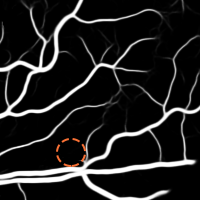

4.1 Validation of the Base System

We started by evaluating our Base System regarding data augmentation, prediction and regularization. The results of each variant are shown in Table 3, while the probabilistic predictions can be seen in Fig. 4. All tests were performed under the same conditions, with the only source of variability being the component under study.

4.1.1 Data Augmentation

To validate the procedure described in Section 2.4, we studied four alternatives. At first, we reduced the total number of patches per image to 3000, by not performing data augmentation – No Augmentation. Then, we increased the total number of patches to 12000 in three different ways. In the first case, we oversampled the image by extracting 9000 more original patches – Oversampling. In the second one, the remaining 9000 patches were artificially created by non-linearly deforming each patch, as described in (Oliveira et al.,, 2017) – Elastic Samples. Each set of 3000 elastic patches was obtained using a different combination: , , or . These values were found manually, ensuring that both the artificial samples and their respective annotations retain a consistent appearance. Finally, we used 9000 rotated patches, as in the Base System, but we placed them consecutively (not randomly) – Consecutive Rotations.

Considering the Base System as the reference, we can see that reducing the number of patches by four strongly deteriorated the results in terms of Acc and AUC. Besides this, either when using original or elastic patches to keep the initial number of samples, the differences to the reference remained almost the same. Looking directly at Fig. 4, we notice that these approaches favored the simultaneous appearance of FN and FP, with elastic patches leading to greater tortuosity in the detected vessel segments. Overall, this hints that the network benefited the most from the information encoded by the rotations. Another important note is related to the way those rotations were presented to the network. Recalling section 2.4, we have seen that some data augmentation strategies designed for FC-CNNs (Dieleman et al.,, 2016; Worrall et al.,, 2016) require the rotated versions to be arranged consecutively. The Consecutive Rotations test hints that a deterministic proximity between the rotated patches is detrimental to the performance of the FCN, with the network showing more difficulties in detecting vessel segments as can be seen in Fig. 4.

When facing the randomly placed rotations used in the Base System, all the alternatives were found to be prejudicial with statistical significance.